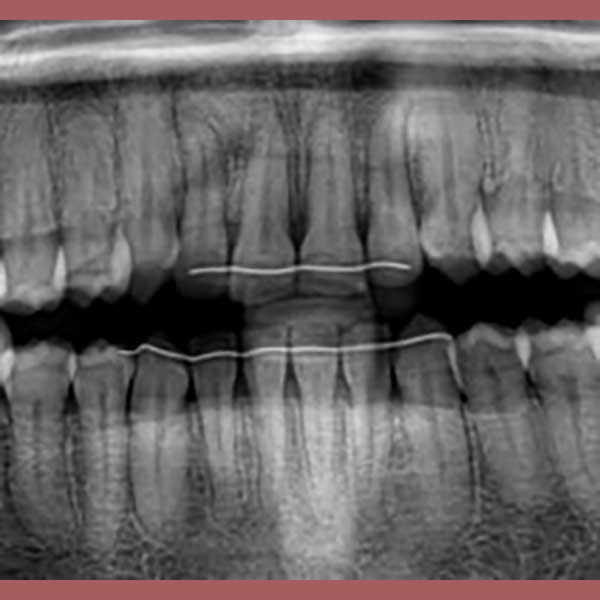

BEFORE

By examining the case and taking X-rays, I observed the upper canines in her mouth, and an embedded lower premolar was observed too on the left side, I started the treat the case, but because of the old age of this lady, the upper canines and the left lower premolar did not erupt on their own after we extracted the temporary canines, and she had to pull them out by braces. As for the lower jaw; The canines were pulled back in place and the embedded premolar was orthodontically pulled.